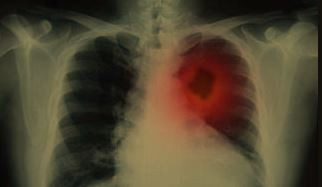

Ракът на белия дроб по правило няма очевидни симптоми, докато туморът започне да метастазира. Поради това възникват трудности с ранната диагностика и в резултат на това с успешното лечение. Има обаче няколко признака, които показват развитието на заболяване в горната част на белия дроб - тумор на Панкост.

Според Cancer Research UK този вид рак причинява много специфични симптоми, най-честите от които са силна болка в рамото. В допълнение промените в лицето могат също да показват наличието на тумор. Сред тях са пролапс на клепачите, малка зеница и липса на изпотяване от едната страна на лицето.

Както обясниха специалистите, тези състояния са причинени от факта, че туморът притиска нерва, идващ от шията. Освен това ракът на белите дробове може да се прояви чрез промени в пръстите. По-специално крайните фаланги доста често се увеличават и ноктите започват да се огъват много. Според Cancer Research UK четири от 10 души с недребноклетъчен рак на белия дроб имат този симптом, но само четири от 100 са с малък клетъчен рак.

Често срещаните симптоми на злокачествен тумор включват постоянна кашлица и утежняване с течение на времето, респираторни инфекции, които периодично се връщат след лечението, болка по време на дишане, постоянни задух, умора, загуба на апетит и тегло.